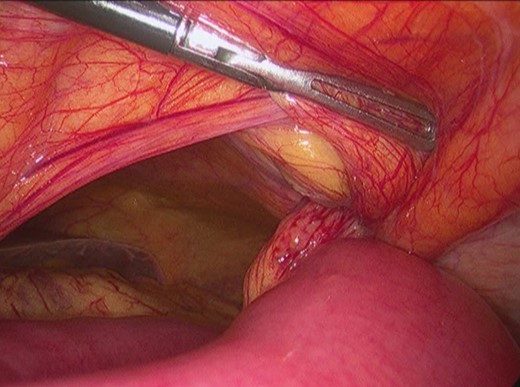

The patient underwent an urgent laparoscopy which showed small bowel herniating through the defect in the left posterior rectus sheath located above the arcuate line (Fig. 4). The hernia was reduced and the defect was repaired laparoscopically with polypropylene/PTFE mesh (Figs 5 and 6). The incarcerated segment of small bowel was edematous with a stenotic and ischemic area and therefore was resected through a small periumbilical incision. The procedure was performed with three incisions (two in rights quadrants and one in umbilical area) (Fig. 7).

Surgery—intraoperative findings: small bowel incarcerated in the left upper abdominal wall hernia.